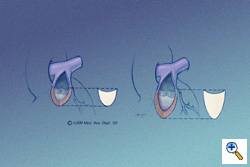

PTFE Monocusp Creation

A bullet-shaped piece of 0.1-mm PTFE (Preclude® pericardial membrane, W.L. Gore & Associates, Flagstaff, AZ) is fashioned as shown. The membrane is placed in the ventricular portion of the opening, allowing it to lay flush along the ventricular walls and conal septum, thereby maximizing surface area coaptation. The edges of the PTFE are traced with a marking pen according to their point of contact with the epicardial surface and the material is cut to the dimensions as outlined. This complements the RVOT anatomic geometry. The illustration on the left shows a short RVOT incision, the illustration on the right shows an extended RVOT incision. The monocusp must be longer, obviously, for a patient with a longer ventriculotomy. This is a key technical point. The monocusp is not constructed to approximate the size of the remaining pulmonary valve leaflets, it is constructed to approximate the size of the ventriculotomy opening. The leading edge of the proposed monocusp is actually flat. It appears curved in these illustrations to show the depth of the leading edge when it fills the RVOT.

A bullet-shaped piece of 0.1-mm PTFE (Preclude® pericardial membrane, W.L. Gore & Associates, Flagstaff, AZ) is fashioned as shown. The membrane is placed in the ventricular portion of the opening, allowing it to lay flush along the ventricular walls and conal septum, thereby maximizing surface area coaptation. The edges of the PTFE are traced with a marking pen according to their point of contact with the epicardial surface and the material is cut to the dimensions as outlined. This complements the RVOT anatomic geometry. The illustration on the left shows a short RVOT incision, the illustration on the right shows an extended RVOT incision. The monocusp must be longer, obviously, for a patient with a longer ventriculotomy. This is a key technical point. The monocusp is not constructed to approximate the size of the remaining pulmonary valve leaflets, it is constructed to approximate the size of the ventriculotomy opening. The leading edge of the proposed monocusp is actually flat. It appears curved in these illustrations to show the depth of the leading edge when it fills the RVOT.